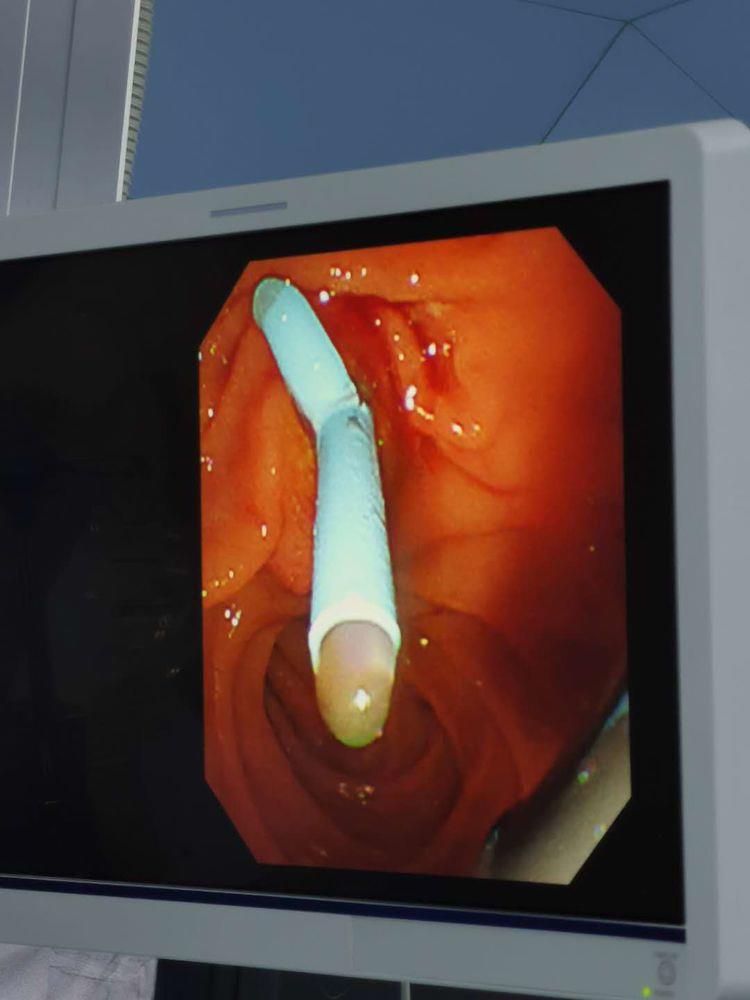

术中:经导丝置入塑料支架,胆汁引流通畅